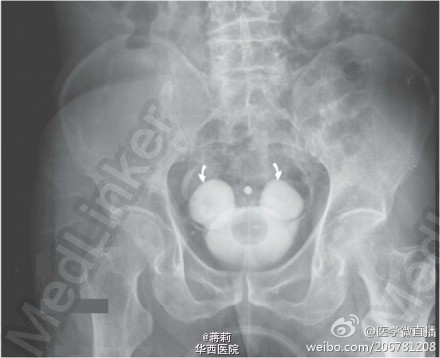

米奇!最快乐的膀胱!

该尿路造影X线片是什么诊断? 答案: 膀胱憩室。该例73岁的男性病人,间歇性发热2周,经常性尿路感染。静脉尿路造影显示尿路没有阻塞,但输尿管开口附近可看到对称憩室。这种病变,称为双雄憩室,通常是先天性的,常见于男性。转自:微博weibo.com